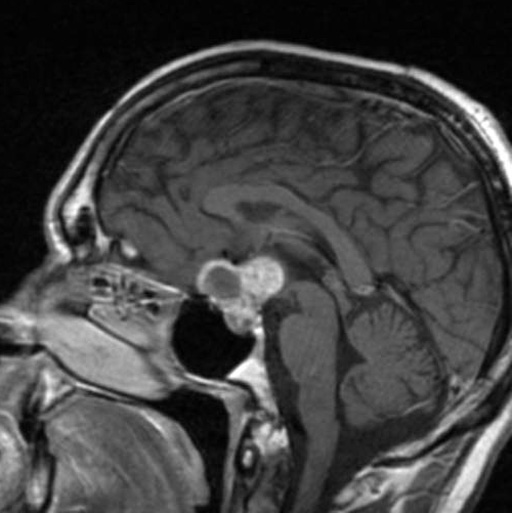

颅咽管瘤通常形成于垂体和下丘脑附近,是一种罕见的脑肿瘤,可能出现在成人和儿童身上。根据肿瘤生长的脑组织不同,可以分为两种亚型:金刚状和乳头状,其中乳头状颅咽管瘤更常见于成人。颅咽管瘤的罕见性在于每年仅有约600人在美国被诊断出患有这种疾病。这些肿瘤虽然不会扩散到身体的其他部位,但由于其侵袭性局部生长以及位于大脑脆弱结构附近,颅咽管瘤可能会导致严重的神经系统症状。此外,它们倾向于附着在重要腺体、大脑结构和血管上,这使得通过手术切除整个肿瘤变得非常具有挑战性。

据统计,颅咽管瘤的患病率非常低,每年仅有约600人在美国被诊断出患有这种疾病。